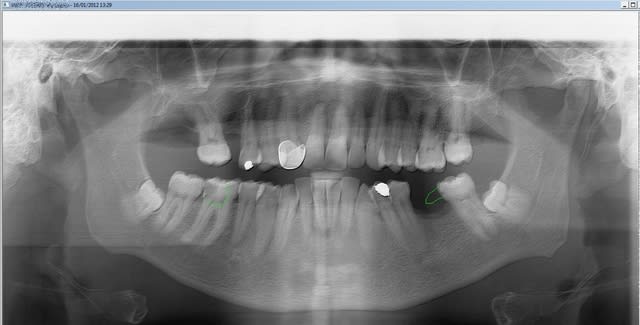

Motif de la consult : carie sur 26 .

Ah ? J'ai des problèmes .

Même pour ça , la 26 est paro donc ext et pas endo . Prudence avant ext. explicage du reste ...il attend pour la pano demandé au rv précédent .

Attention , j'ai volontairement déporté votre attention en haut mais en bas ...

Patient vu il y a 5 ans , et plus rien . J'ai donc traité dans l'urgence mais quoi donc ?